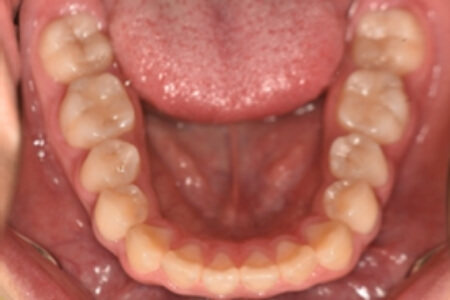

動的治療終了時

症例 症例 症例 症例 症例

治療としては、非抜歯の上、マウスピース矯正装置(インビザライン)で配列を行いました。顎間ゴムの協力もあり、咬み合わせがきれいに改善されました。

治療期間は1年11か月でした。